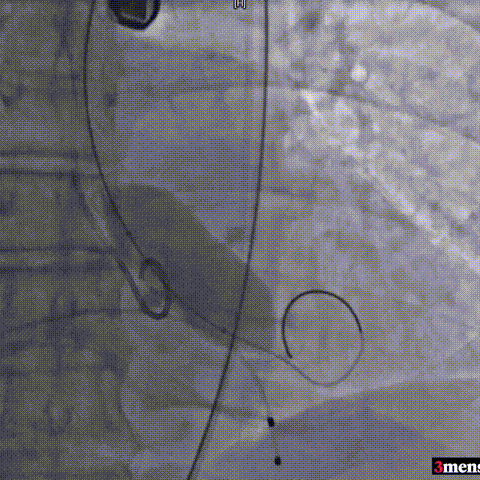

手术过程回顾:

主动脉根部造影

直头导丝跨瓣

球囊预扩

输送器过弓

瓣膜定位

瓣膜释放至工作位

瓣膜脱钩

球囊后扩